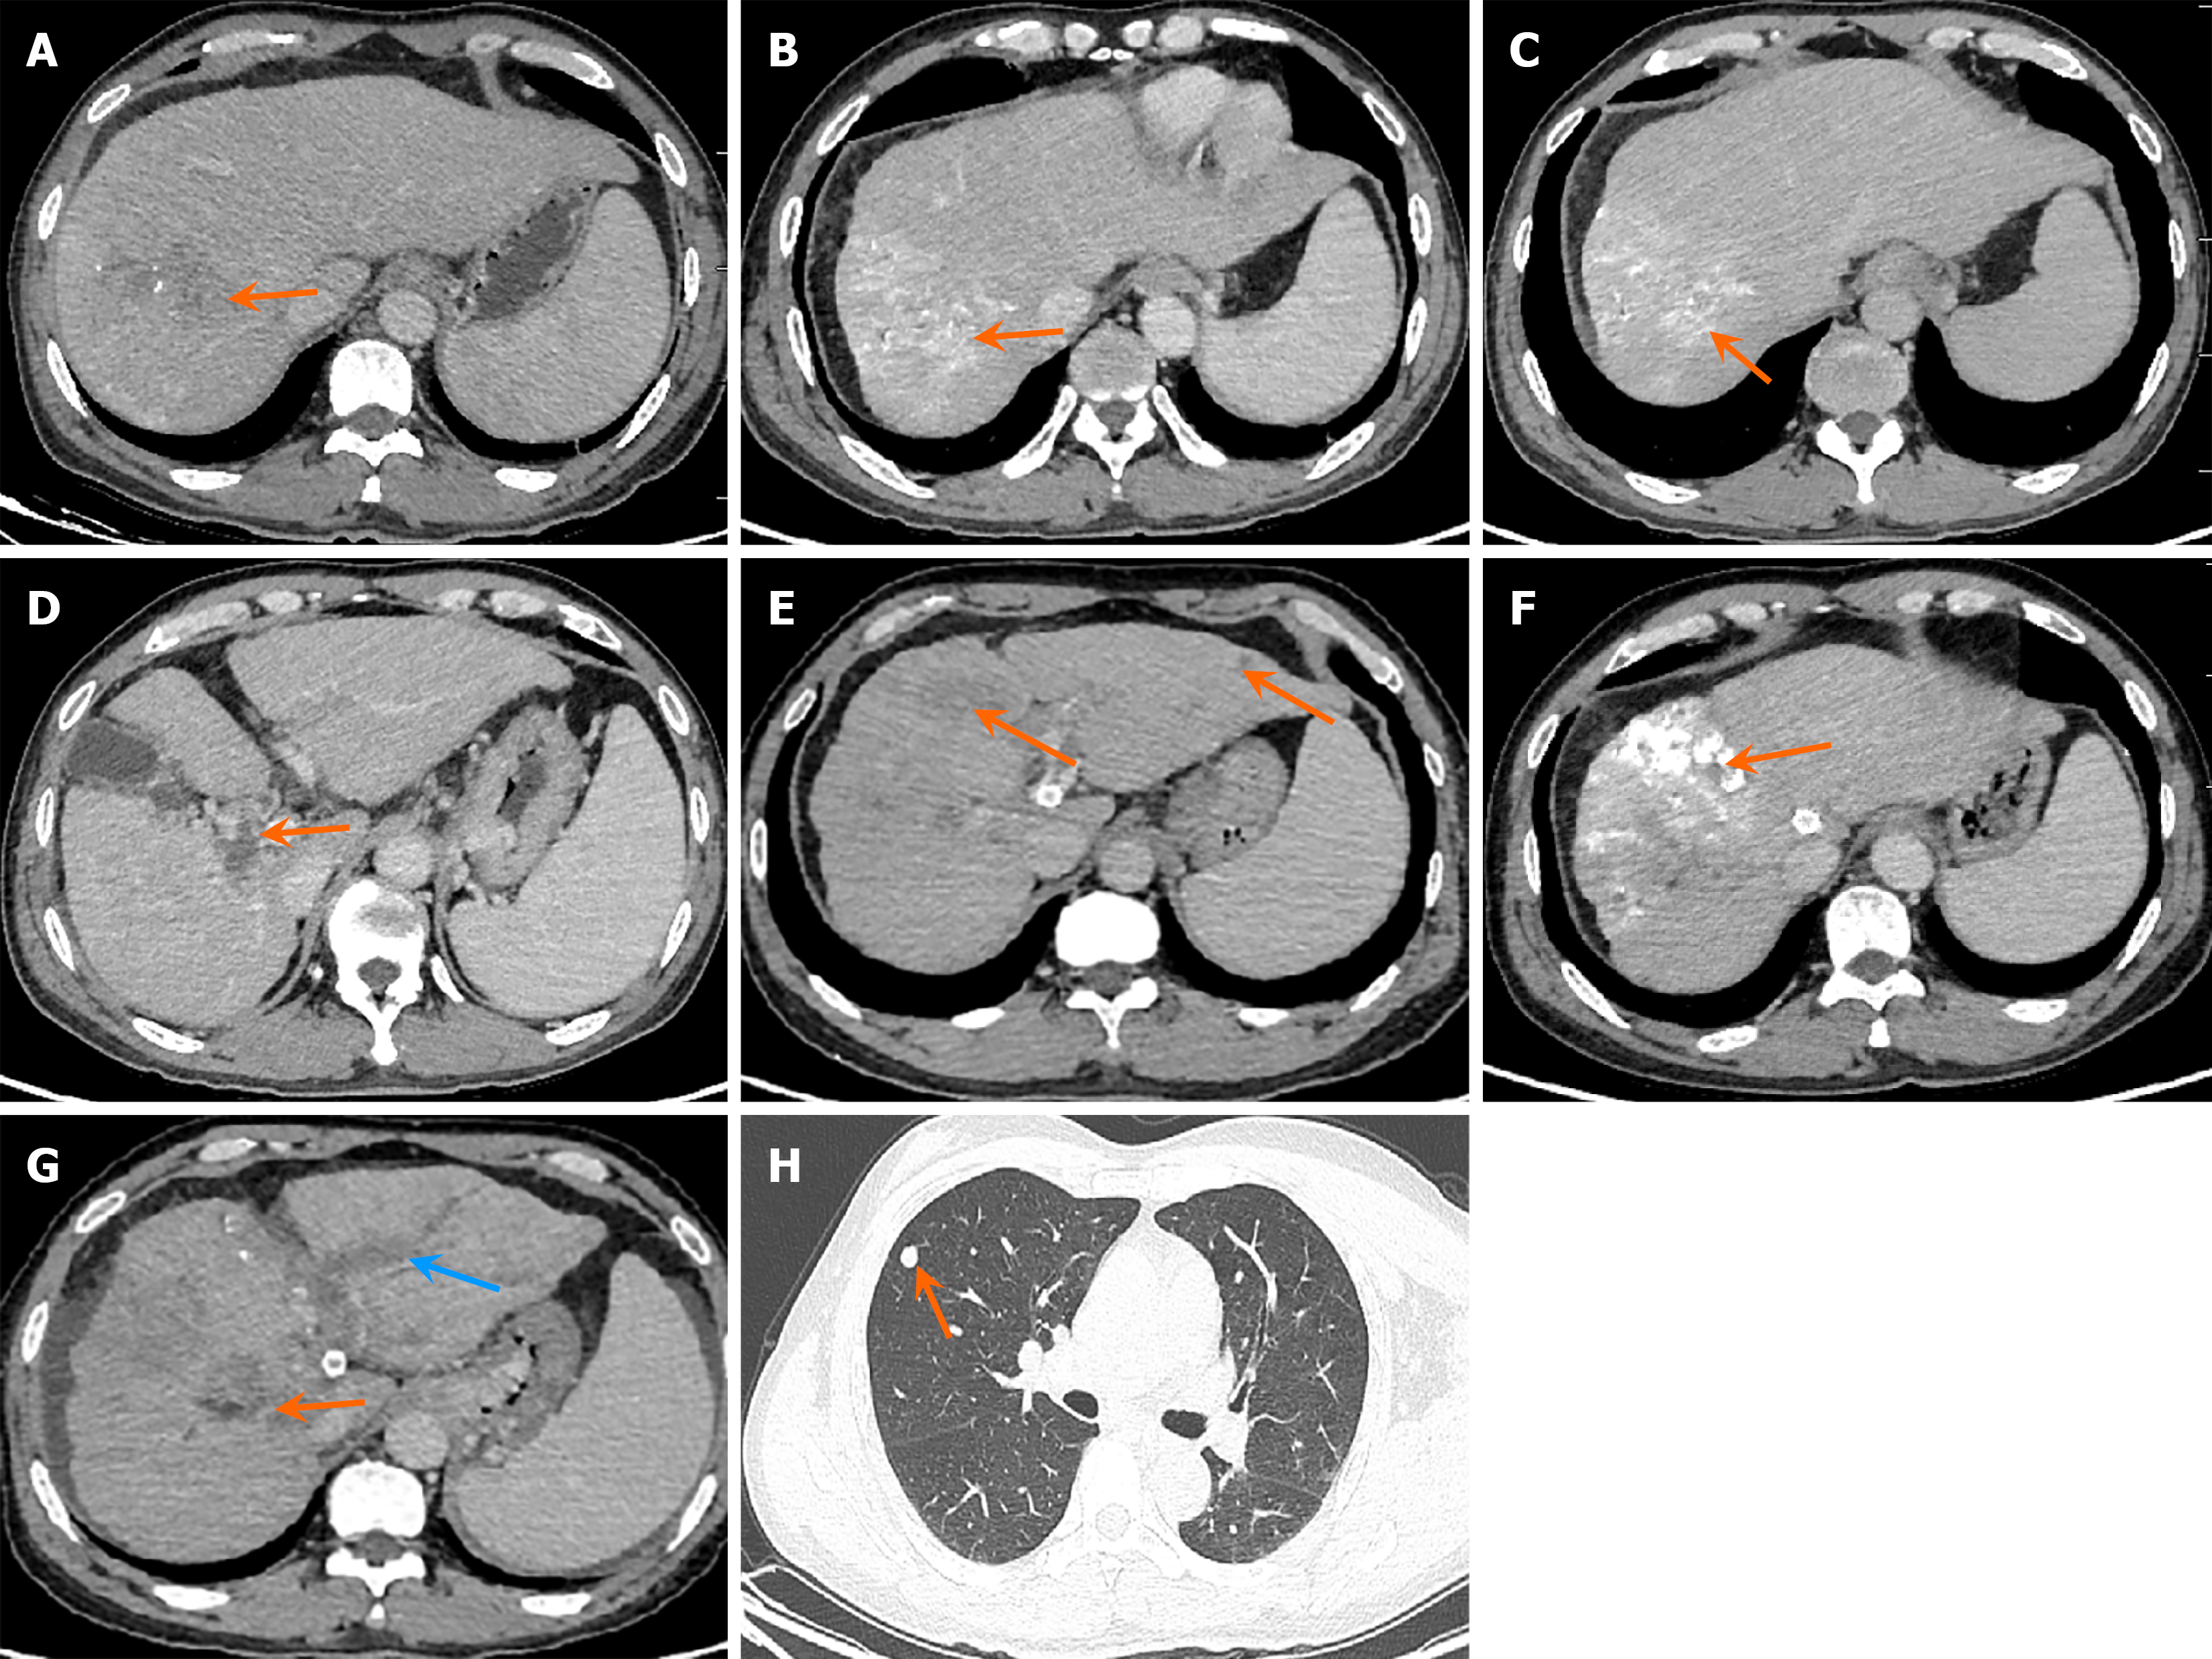

Figure 2 Computed tomography changes after hepatic artery infusion chemotherapy treatment.

A: Tumor shrinkage after one cycle of hepatic artery infusion chemotherapy (HAIC) (orange arrow); B: After six cycles of HAIC combined with lipiodol embolization (orange arrow); C: No bile duct dilatation after six cycles (orange arrow); D: Portal vein tumor thrombus decreased in size after six cycles (orange arrow); E: Tumor progression with new intrahepatic lesions after 20 months (orange arrow); F: Good lipiodol deposition after transarterial chemoembolization (orange arrow); G: Tumor progression with new lesions after 28 months, with portal vein tumor thrombus in the right branch and bile duct obstruction (blue arrow); H: Pulmonary metastases (orange arrow).